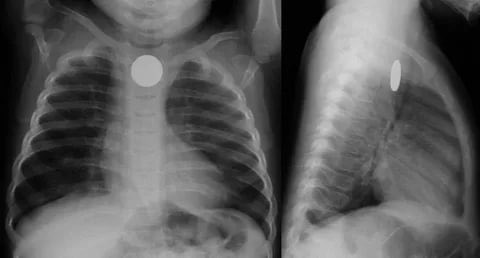

🔰من المهم جداً ان نتطرق الى مخاطر البطاريات :

معظم حالات ابتلاع البطاريات تكون خطيرة .هناك حالات أدّت للوفاة أو لحدوث حرق أو ثقب في المريء أو القصبة الهوائية مصحوباً بمضاعفات خطيرة ، كالحاجة لتدخل جراحي

هذه المضاعفات تحدث عندما تعلق البطارية في المريء ولا يتم إزالتها خلال ساعتين ، حيث تشكل ما يشبه السائل الكاوي الذي يتسبب في تسمم الأطفال . وضع البطارية في الأنف أو الأذن يعدّ أيضاً أمراً خطراً ويستدعي إزالة البطارية في أسرع وقت .